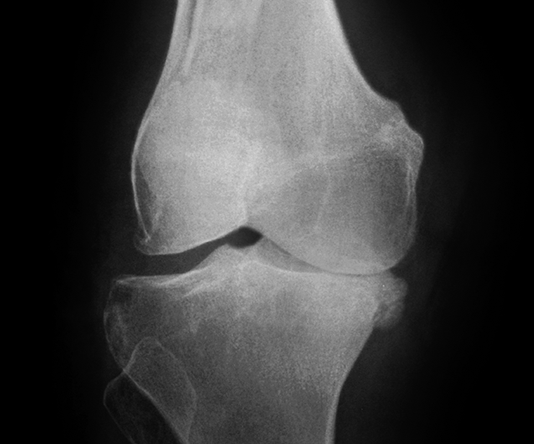

3. Giai đoạn 3: Thoái hóa khớp gối độ 3

Hình ảnh của khớp gối trên phim X-quang: Khe khớp hẹp rõ, nhiều gai xương kích thước vừa, đặc xương dưới sụn, đầu xương có thể bị biến dạng.

Thoái hóa khớp gối tiến triển đến giai đoạn 3 thì bệnh nhân sẽ càng cảm nhận rõ những cơn đau tại khớp gối. Các lớp sụn khớp bao bọc các đầu xương bị bào mòn nhiều và khoảng không gian giữa các đầu xương bị thu hẹp thấy rõ. Khả năng đi bộ của người bệnh giảm, đi, đứng, ngồi xổm, lên xuống cầu thang cũng thấy đau. Tình trạng cứng khớp vào buổi sáng cũng xảy ra thường xuyên hơn kèm theo các đợt viêm khớp gối (sưng, đau, tràn dịch) hoặc có biểu hiện vẹo khớp gối.